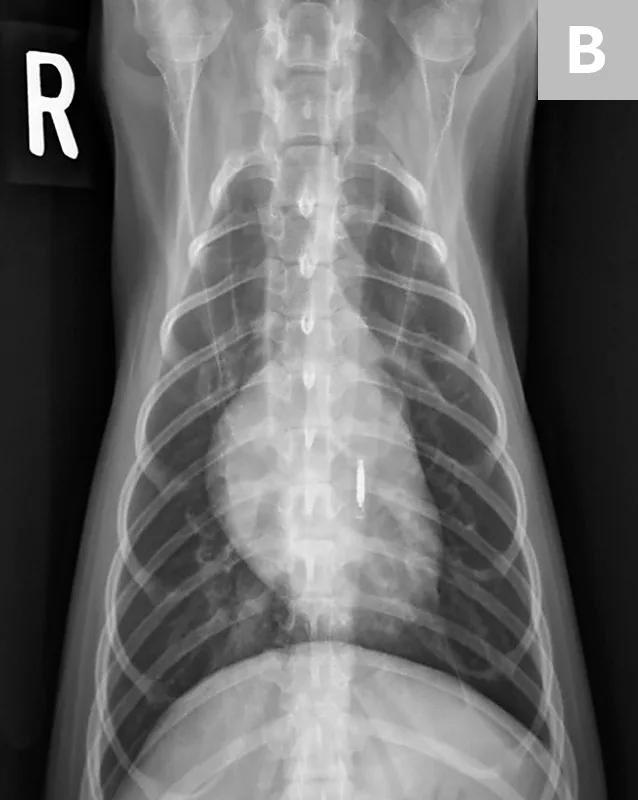

• Place the patient in dorsal recumbency for the ventrodorsal view. For ease in positioning, a V-trough helps keep the spine and sternum aligned and is more comfortable for the patient. With the head straight, tie the thoracic limbs cranially and the pelvic limbs caudally. Place a thin sandbag across the neck or on either side of the head if help is needed with restraint and positioning. The head and neck need to be straight, not turned to the side. (See Figure 4.)

• Make sure the sternum and dorsum are superimposed on the radiograph. If the spinous processes are visible pointing to one side, move the sternum in the direction they are pointing to straighten the spine and sternum. (See Figure 5.)